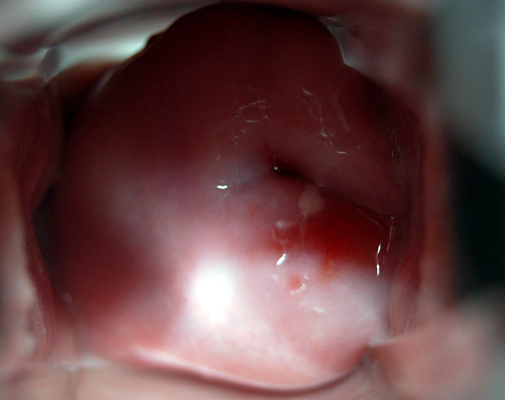

子宮肥大圖片

子宮肥大圖 (7)